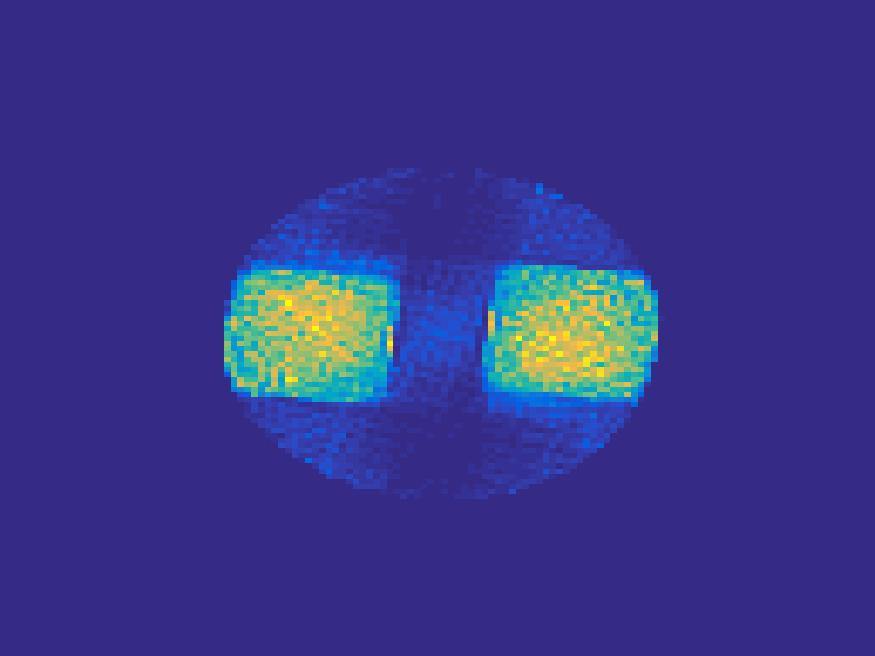

The proposed method is tested on numerical phantoms for a proof of concept study. We simulate image frames of size and projections per frame. Three time activity curves (TAC) for blood, liver and myocardium, previously used in [14] (see Figure 1), are used to simulate the dynamic images. The first simulated dynamic phantom is composed of two ellipses. In temporal direction, the positions of the two ellipses are stationary while the intensity in 90 frames within the region of each ellipse is generated according to the TAC of blood or liver. The projections are generated by using Radon transform sequentially performed for each frame.

In the tests, projections at two orthogonal angles are simulated for every frame to mimic 2-head camera data collection. The projection angles increase sequentially by along temporal direction. For example, at frame 1, projections are simulated at angle and , and at frame 2, angle and , etc. Finally, white Gaussian noise is added to the projection data. Reconstruction results with different methods are shown in Figure 3. Since the number of projections is very limited for each frame, the traditional FBP and least square methods cannot reconstruct the images satisfactorily, while the proposed method is capable to reconstruct the images effectively. Compared with SEMF model, when the edge of images jump (see frame 21 -frame 31 in Figure 3), the proposed model can better capture the change of the tendency of TAC.

| Frame 1 | Frame 11 | Frame 21 | Frame 31 | Frame 41 | Frame 51 | Frame 61 | Frame 71 | Frame 81 |